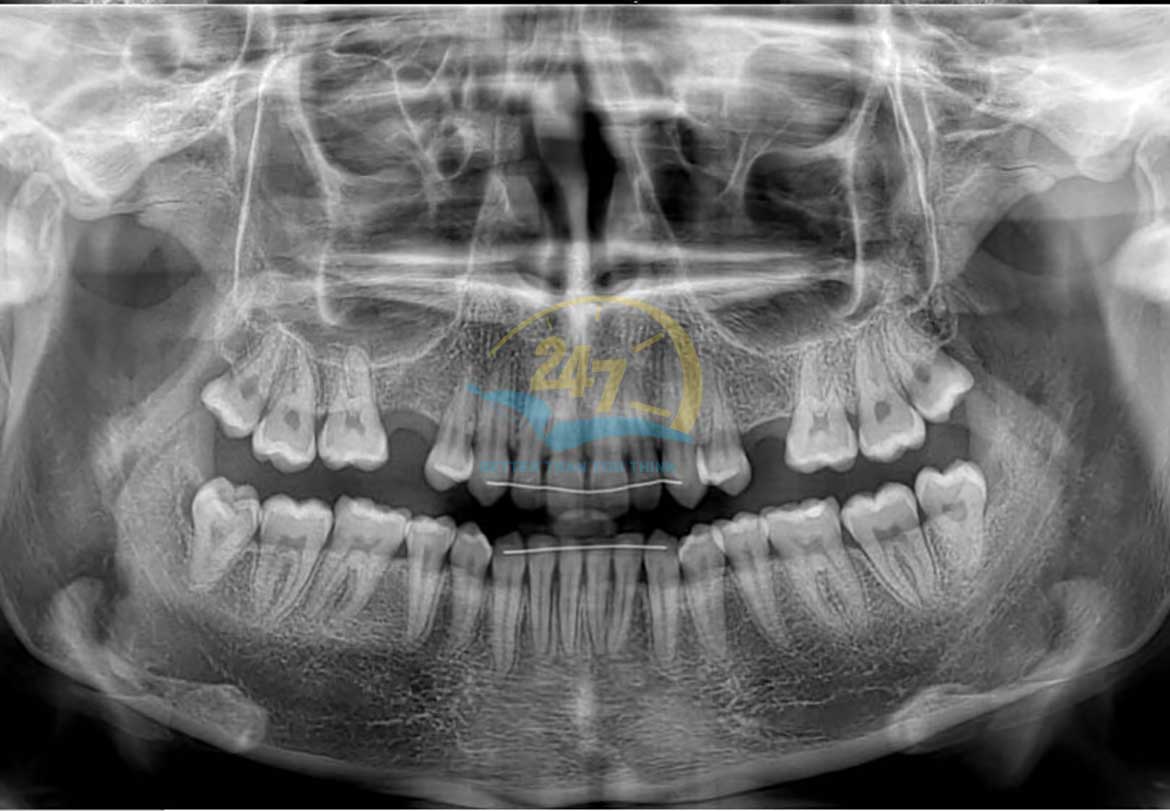

Được biết, chụp X-quang 2D là thiết bị có thể ghi lại toàn bộ hình ảnh của răng miệng bao gồm: răng, hàm trên, hàm dưới, cấu trúc và các mô xung quanh. Căn cứ vào những hình ảnh hai chiều, bác sĩ sẽ có cái nhìn tổng quát nhất, từ đó dễ dàng đưa ra phương hướng điều trị thích hợp.

Chụp X-quang 2D có thể chụp lại toàn bộ hình ảnh từ bên trong đến bên ngoài miệng. Với từng trường hợp cụ thể, bác sĩ sẽ chỉ định cách chụp phù hợp như:

Bác sĩ sẽ yêu cầu chụp X-quang ngoài miệng khi cần theo dõi tình trạng phát triển của hàm răng, phát hiện u nang, khối u hoặc vấn đề về tuyến nước bọt. Một số loại X-quang ngoài miệng bao gồm: Chụp cắt lớp, chụp toàn cảnh, chụp sinogram, chụp cắt lớp vi tính, chụp ảnh kỹ thuật số,…